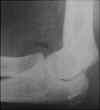

Visualization of a lipohemarthrosis in the elbow is joint is rare. It can only be seen radiographically on lateral views of the elbow with intraarticular fractures. It can be seen with CT, but this examination is not performed often in the acute setting. A more common finding in the acutely injured elbow is a displaced fat pad. This sign was first described in 1954. Often, subtle fractures of the radial head cannot be detected radiographically, but their presence can be inferred due to the presence of a joint effusion (blood) which on the lateral view of the elbow, displaces the anterior (coronoid) and posterior (olecranon) fat pads away from the joint. It is commonly believed that the presence of a displaced posterior fat pad is a more sensitive indicator of occult fracture than displacement of the anterior fat pad. Approximately 5 - 15 cc of fluid is required to displace these two fat pads so that they are radiographically detectable. The anterior fat pad should only be barely perceptible in the normal elbow. Case1: A 30 year old male fell while playing tennis. Image 1: The lateral radiograph of the elbow demonstrates the presence of abnormal anterior and posterior fat pads, due to the presence of blood within the joint from a nondisplaced radial head fracture. CLICK TO ENLARGE. Case 2: A 13 year old boy fell while playing soccer. Image 1: This lateral radiograph of the elbow demonstrates a true lipohemarthrosis of the elbow joint. Again, there is a crescent shaped region of low density anterior to the radial head. This corresponds to fat which has migrated from the marrow space to the joint space through an intraarticular fracture. The fracture itself is not visible. CLICK TO ENLARGE.